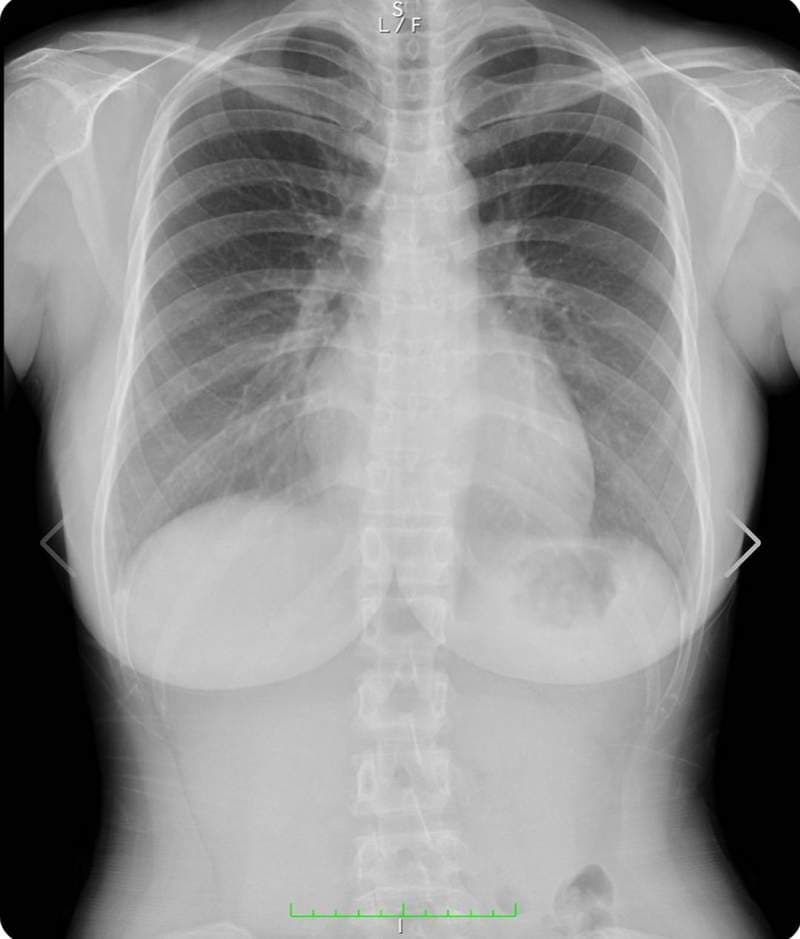

至于今天开头跟大家分享的上空X光照,大家千万不要觉得阿漆又要唬烂骗点阅,实际上她在最近真的有公开自己的X光照片,其实她在之前8月的时候曾确诊新冠肺炎,休养一个月之后康复已经完全健康,现在做个体检也是确认不要有后遗症

另外之前有网友曾质疑她胸部作假,这么大肯定不是天然的胸部,而这次在社群媒体上公开自己的体检结果,也间接打脸掉这个说法,她的胸部没有任何填充物,而右胸上小小的黑点是胃泡,所以整体检查结果下来是很OK的